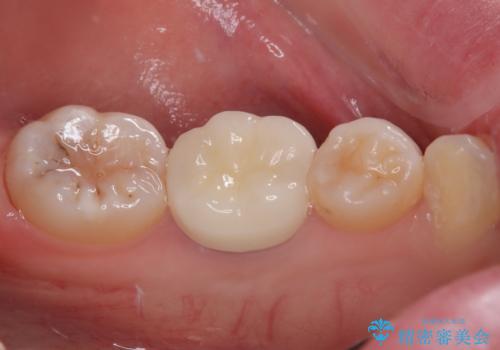

明るく自然な口元になりました。

奥歯も著しく茶色に変色していたため、同様にオールセラミッククラウンにて補綴治療を行うこととしました。